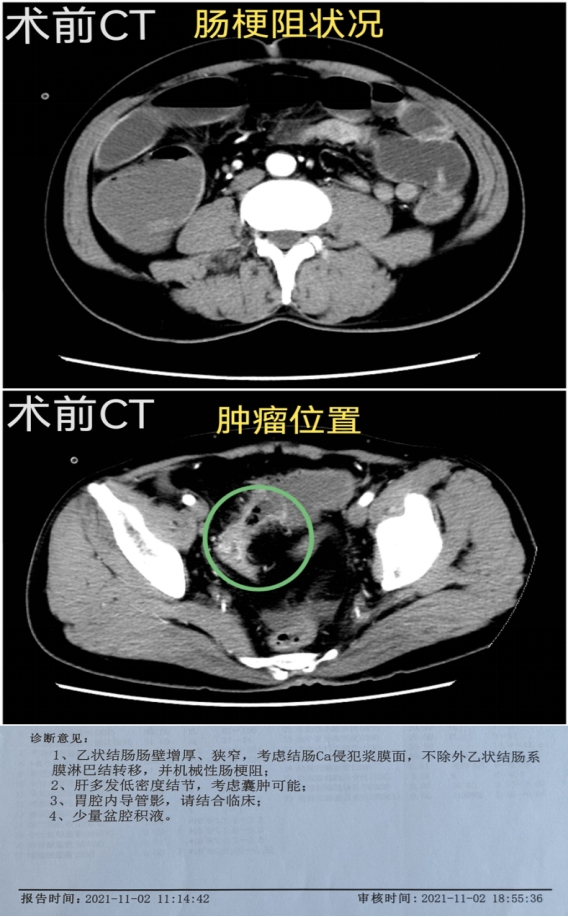

直肠上段及乙状结肠是肠癌的高发部位,此处肠管较细,极易发生肠梗阻。2021年11月2日,我院胃肠外科收治了一名肠梗阻患者,当日完成腹部增强CT,次日完成局部肠镜检查,诊断为乙状结肠癌伴机械性肠梗阻,肠镜无法通过肿瘤狭窄肠腔。经洗肠通便对症治疗后,患者肠梗阻症状有所好转。由于患者家庭情况特殊及经济条件等因素,要求尽快给予手术。考虑患者因术前合并有肠梗阻,肠管质量及条件一般,术后吻合口瘘的发生概率很高,术前给予拟定行腹腔镜下保留左结肠动脉和直肠上动脉的乙状结肠癌根治术,以最大程度保留血管保证吻合口血运,确保患者术后吻合口瘘的发生率降到最低。